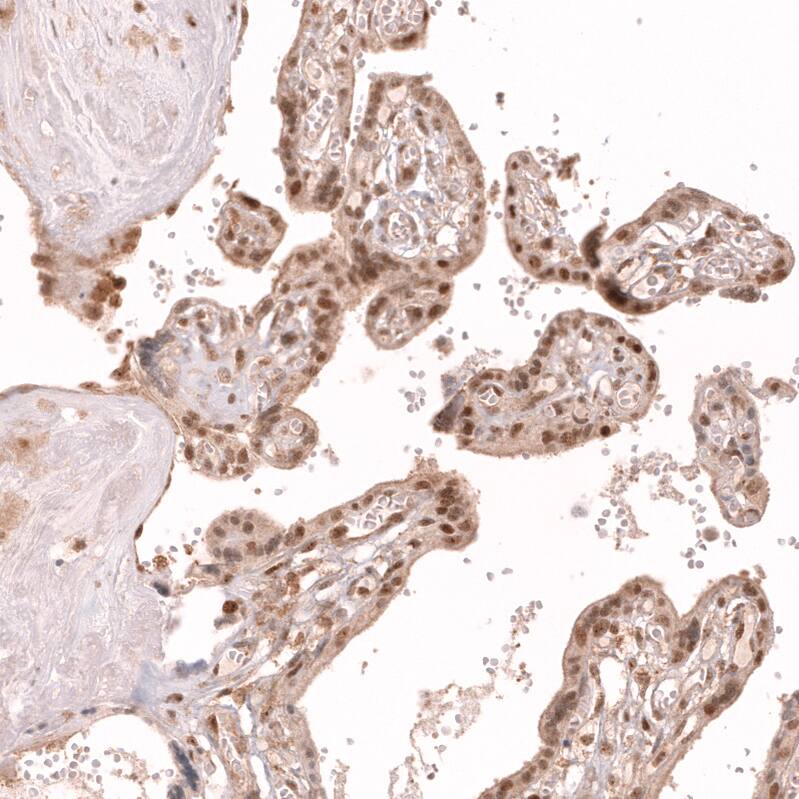

Staining of human placenta shows strong nuclear positivity in trophoblastic cells.